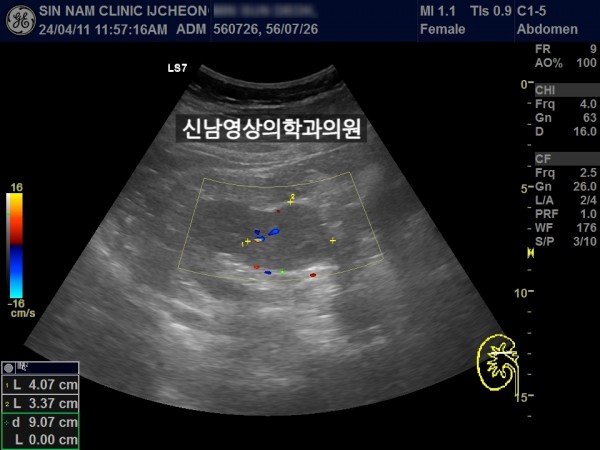

좌측 신장 지방혈관종 추적검사中 우측 신장의 종괴를 발견했습니다.

차후 신장암으로 수술하셨습니다.

초음파 당시 증세는 없었습니다.